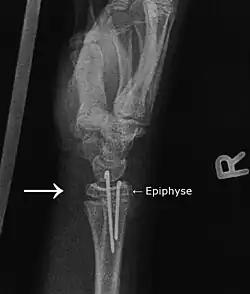

Das rechte Bild zeigt die Situation nach der Operation. Hier wurden Drähte (sogenannte Kirschnerdrähte) von handseitig während der Reposition (Wieder-in-Position-Bringen) durch die Epiphyse in den Radiusschaft gebohrt. Der Radius steht jetzt nicht mehr nach palmar vor. Die Kirschnerdrähte verbleiben, bis die Epiphyse wieder festgewachsen ist (2–4 Wochen).